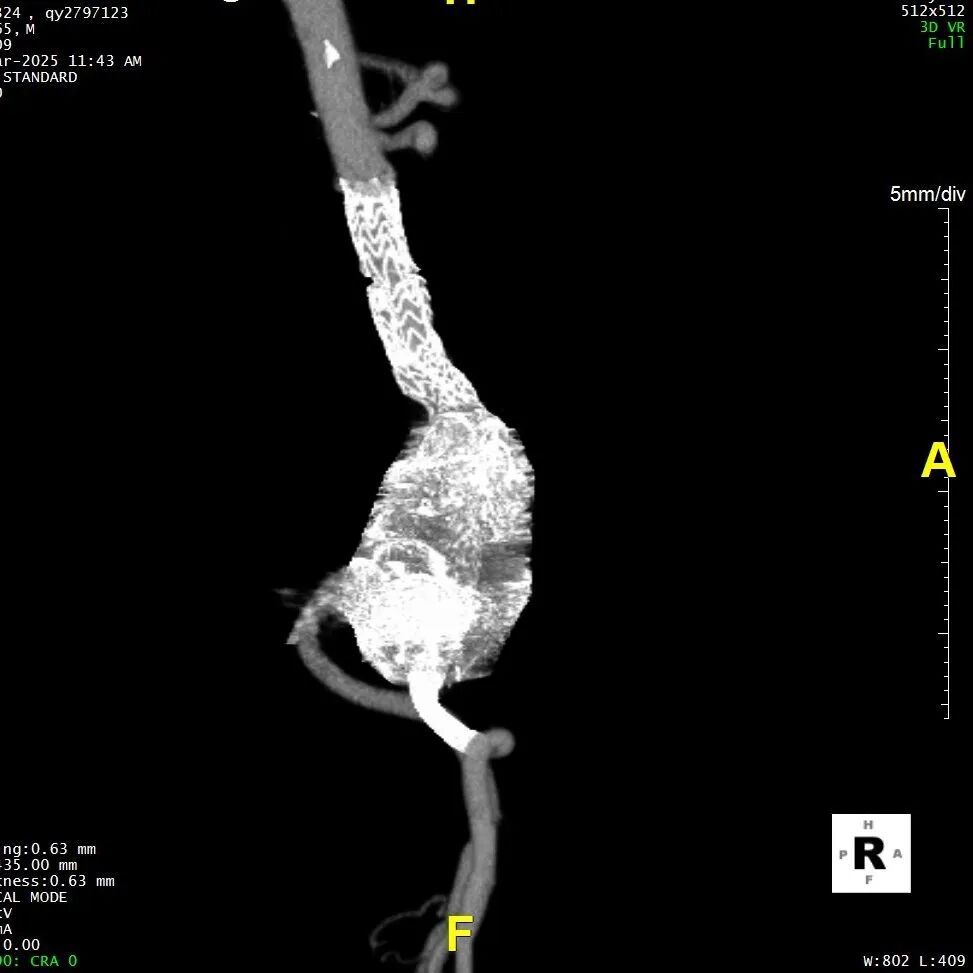

五、术后随访

患者术后进行随访,支架形态良好,瘤体隔绝良好,分支血管通畅,预后满意。

gore医疗怎么样「漫腹精论」髂合时宜 精益求精——双MOB球囊导管辅助腹主动脉覆膜支架急诊治疗破裂巨大髂动脉瘤_https://www.jmylbn.com_新闻资讯_第28张

gore医疗怎么样「漫腹精论」髂合时宜 精益求精——双MOB球囊导管辅助腹主动脉覆膜支架急诊治疗破裂巨大髂动脉瘤_https://www.jmylbn.com_新闻资讯_第29张

gore医疗怎么样「漫腹精论」髂合时宜 精益求精——双MOB球囊导管辅助腹主动脉覆膜支架急诊治疗破裂巨大髂动脉瘤_https://www.jmylbn.com_新闻资讯_第30张

gore医疗怎么样「漫腹精论」髂合时宜 精益求精——双MOB球囊导管辅助腹主动脉覆膜支架急诊治疗破裂巨大髂动脉瘤_https://www.jmylbn.com_新闻资讯_第31张

gore医疗怎么样「漫腹精论」髂合时宜 精益求精——双MOB球囊导管辅助腹主动脉覆膜支架急诊治疗破裂巨大髂动脉瘤_https://www.jmylbn.com_新闻资讯_第32张

gore医疗怎么样「漫腹精论」髂合时宜 精益求精——双MOB球囊导管辅助腹主动脉覆膜支架急诊治疗破裂巨大髂动脉瘤_https://www.jmylbn.com_新闻资讯_第33张

gore医疗怎么样「漫腹精论」髂合时宜 精益求精——双MOB球囊导管辅助腹主动脉覆膜支架急诊治疗破裂巨大髂动脉瘤_https://www.jmylbn.com_新闻资讯_第34张